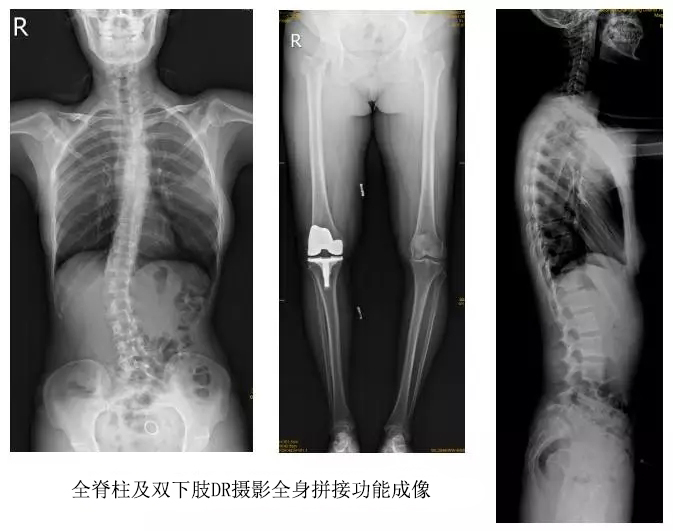

技術(shù)日新月異,隨著DR全身拼接功能的可實(shí)現(xiàn),有效解決了全脊柱及全下肢的完整成像。

以某院所攝X光片為例,對(duì)比傳統(tǒng)攝片與全身拼接功能的區(qū)別:

傳統(tǒng)X光片只能觀察每個(gè)部位的局部情況,無(wú)法在統(tǒng)一體上進(jìn)行連續(xù)、全面的觀察,全脊柱及下肢全長(zhǎng)片則能直觀的看到整體形變。通過(guò)DR全身拼接功能實(shí)現(xiàn)的完整成像,為診治脊柱及下肢畸形提供了完美的臨床影像依據(jù),對(duì)臨床診斷、術(shù)前手術(shù)方案的制定和術(shù)后療效的評(píng)估等臨床應(yīng)用具有十分重要的意義,有效滿足了此類疾病臨床診斷和治療的要求。